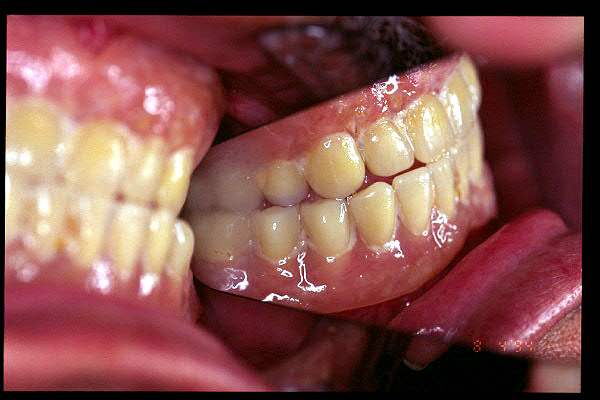

CM Extrusión de incisivos inferiores por falta de contactos oclusales